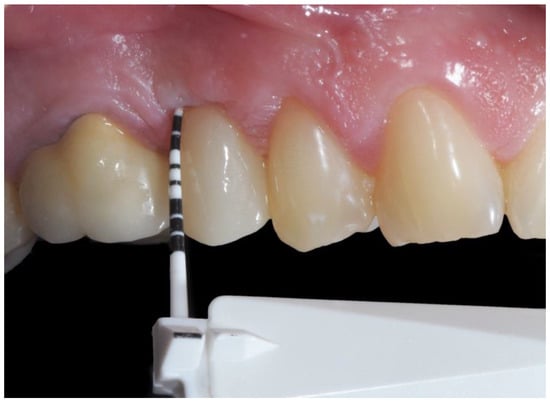

2.5. Clinical Evaluations